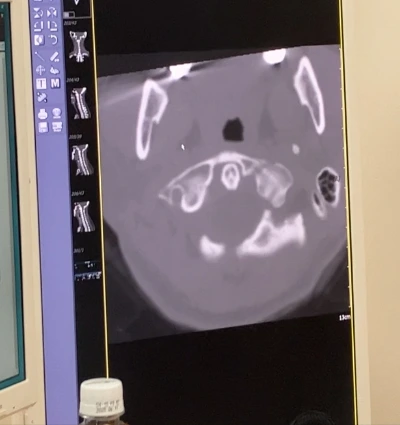

이번이 4번째 ct죠?

같이 사진 한 번 볼게요.

음….

뭐 비슷하네요.

저번달과 비슷해요

붙고는 있어요. 근데 너무… 더뎌.

이게 뼈가 부러질 때 워낙

크게 박살이 난 대다

절단면도 클리어하게 깔끔하지 않고

뼛조각이 날라가 버렸으니

뼈와 뼈 사이의 공간, 갭이

너무 커요. 이게 더딜 수 밖에 없어…”